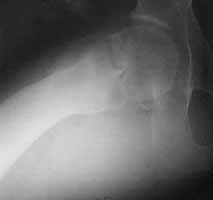

A male 31 years old treated elsewhere after not severe pelvic fracture 2 months ago, was managed non operatively. So the injury looked as a reason of his inability to elevate the leg. However at the recent x-rays the neck fractire was found. The patient already has been walking with partial weight-bearing.

Looking at the x-rays and the time since the injury, what is the optimal treatment for now? We discussed 1)leave as is, 2)2 cancellows screws as is, 3)valgus osteotomy. Total hip replacement looks unnecessary yet.